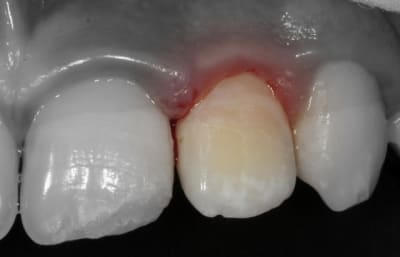

Le fragment fracturé, récupéré par la maman, est collé.

- Le collage du fragment coronaire peut se faire même très longtemps après la fracture (plusieurs semaines) : on le conserve dans du sérum physiologique, au frigo, pour éviter un aspect déshydraté.

Mordançage et adhésif sur la dent et sur le fragment. Si le fragment s'adapte parfaitement, l'adhésif est polymérisé quand le fragment est en place. Si l'adaptation n'est pas parfaite (léger hiatus par endroit), je polymérise l'adhésif avant puis utilise du composite fluide entre le fragment et la dent.

- Pour la pose de la biodentine : le matériau est tixotrope, il se fluidifie dès qu'on le vibre. Je le place dans la cavité puis en le tapotant délicatement, il "fond" et se répartit sans qu'on ait à le fouler.

- Le volume de Biodentine est dans la chambre et n’interfère donc pas avec le collage : j'ai juste nettoyé le pourtour et fraisé l'excès sur le dessus.